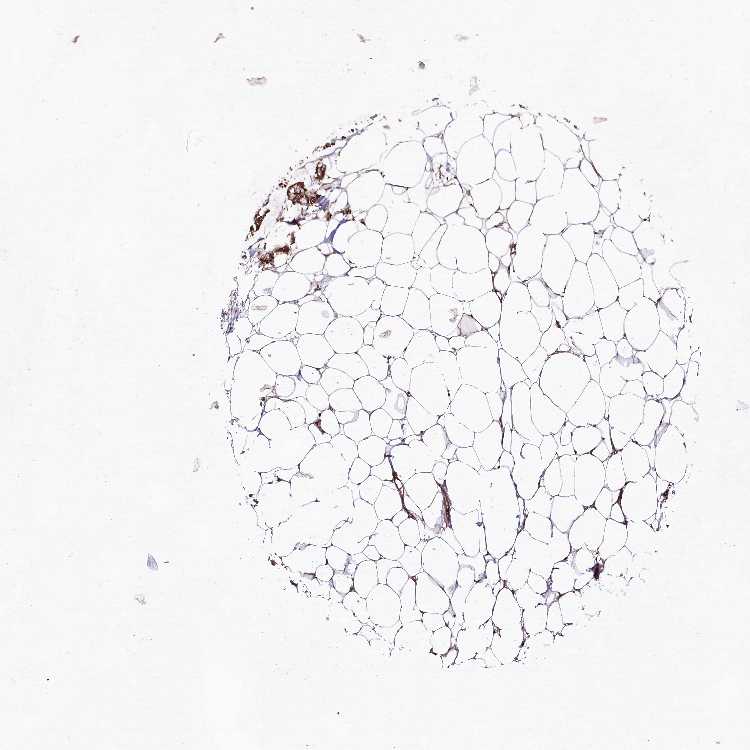

SOFT TISSUE 1 - Antibody stainingi

Antibody staining in the annotated cell types in the current human tissue is reported as not detected, low, medium, or high, based on conventional immunohistochemistry profiling in selected tissues. This score is based on the combination of the staining intensity and fraction of stained cells.

Each image is clickable and will lead to virtual microscopy that enables deeper exploration of all samples and also displays staining intensity scores, fraction scores and subcellular localization as well as patient and tissue information for each sample.

Antibody HPA037489

Fibroblasts Not detected

Peripheral nerve Not detected

SOFT TISSUE 2 - Antibody stainingi

Peripheral nerve Low